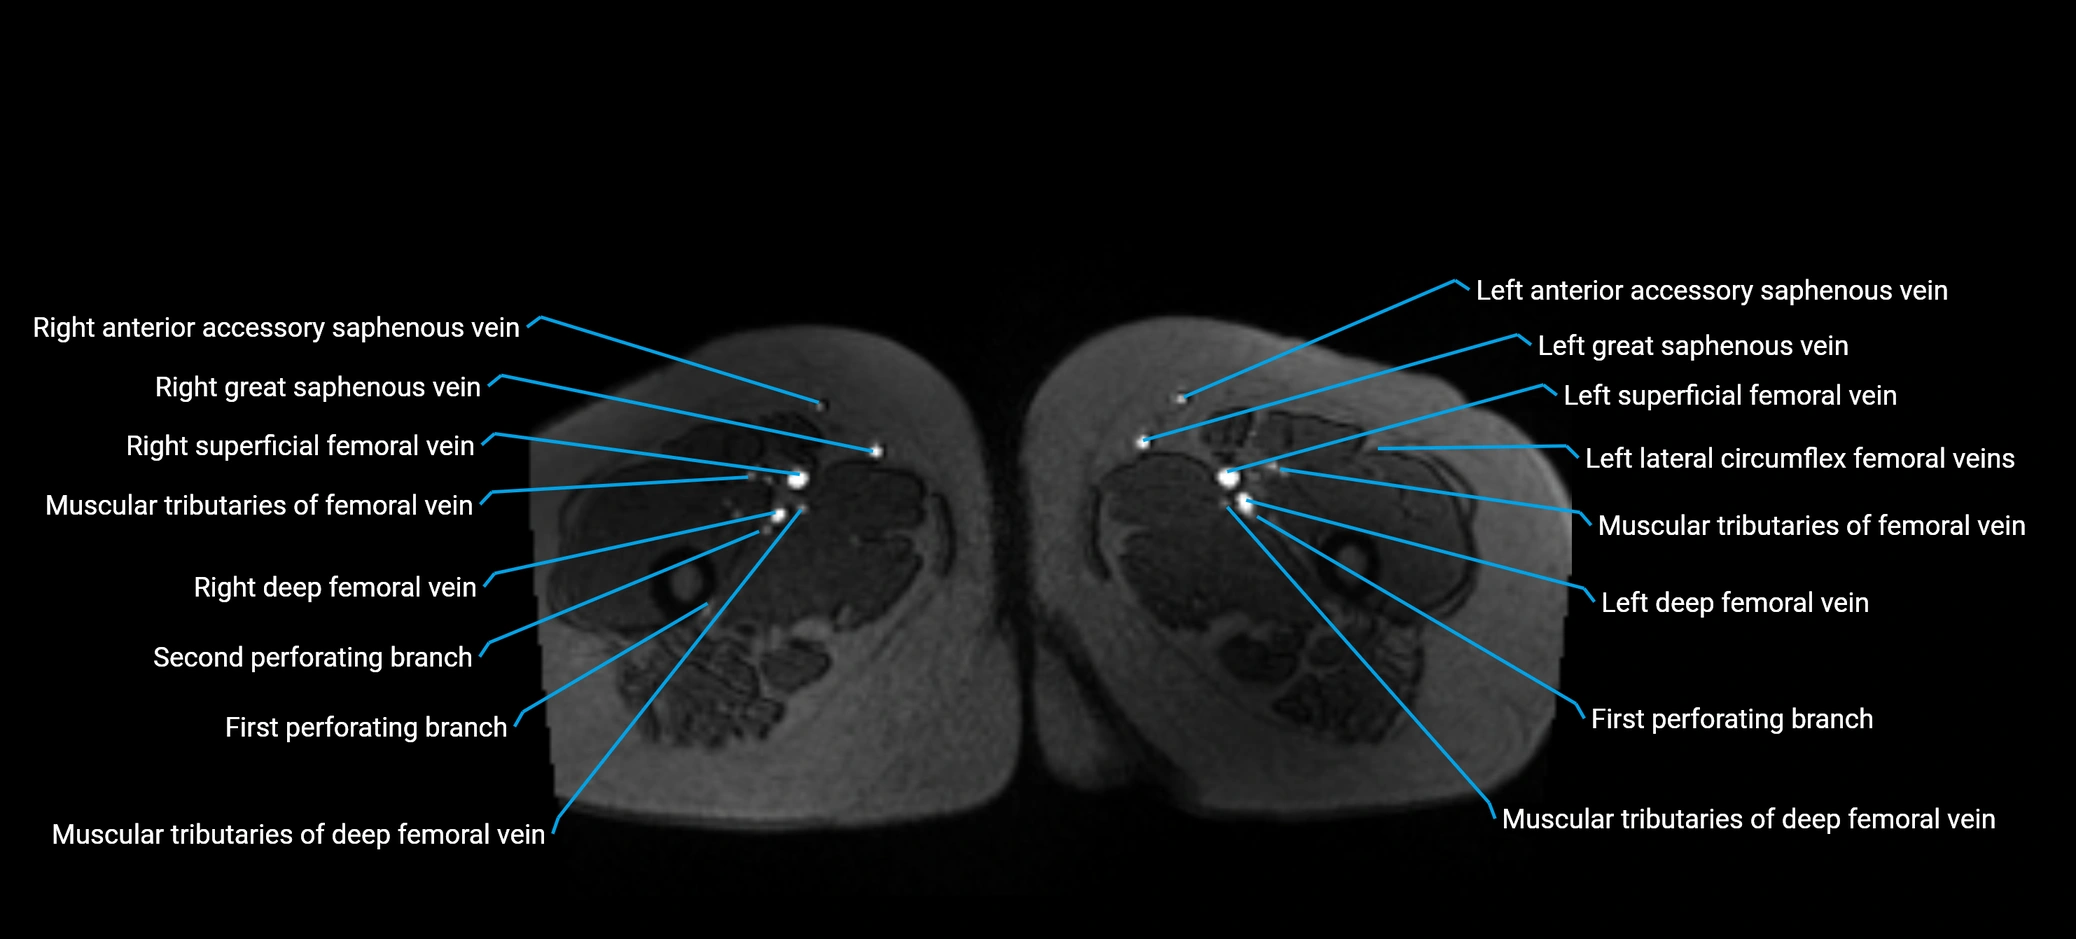

MRI image

image